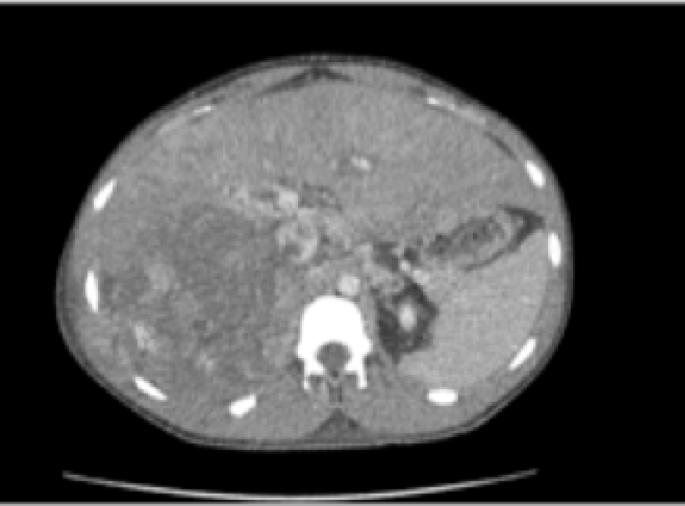

What is the next appropriate step in this patient with a renal tumor and peritoneal implants?

Given the stage, the most appropriate initial treatment of this renal mass would be